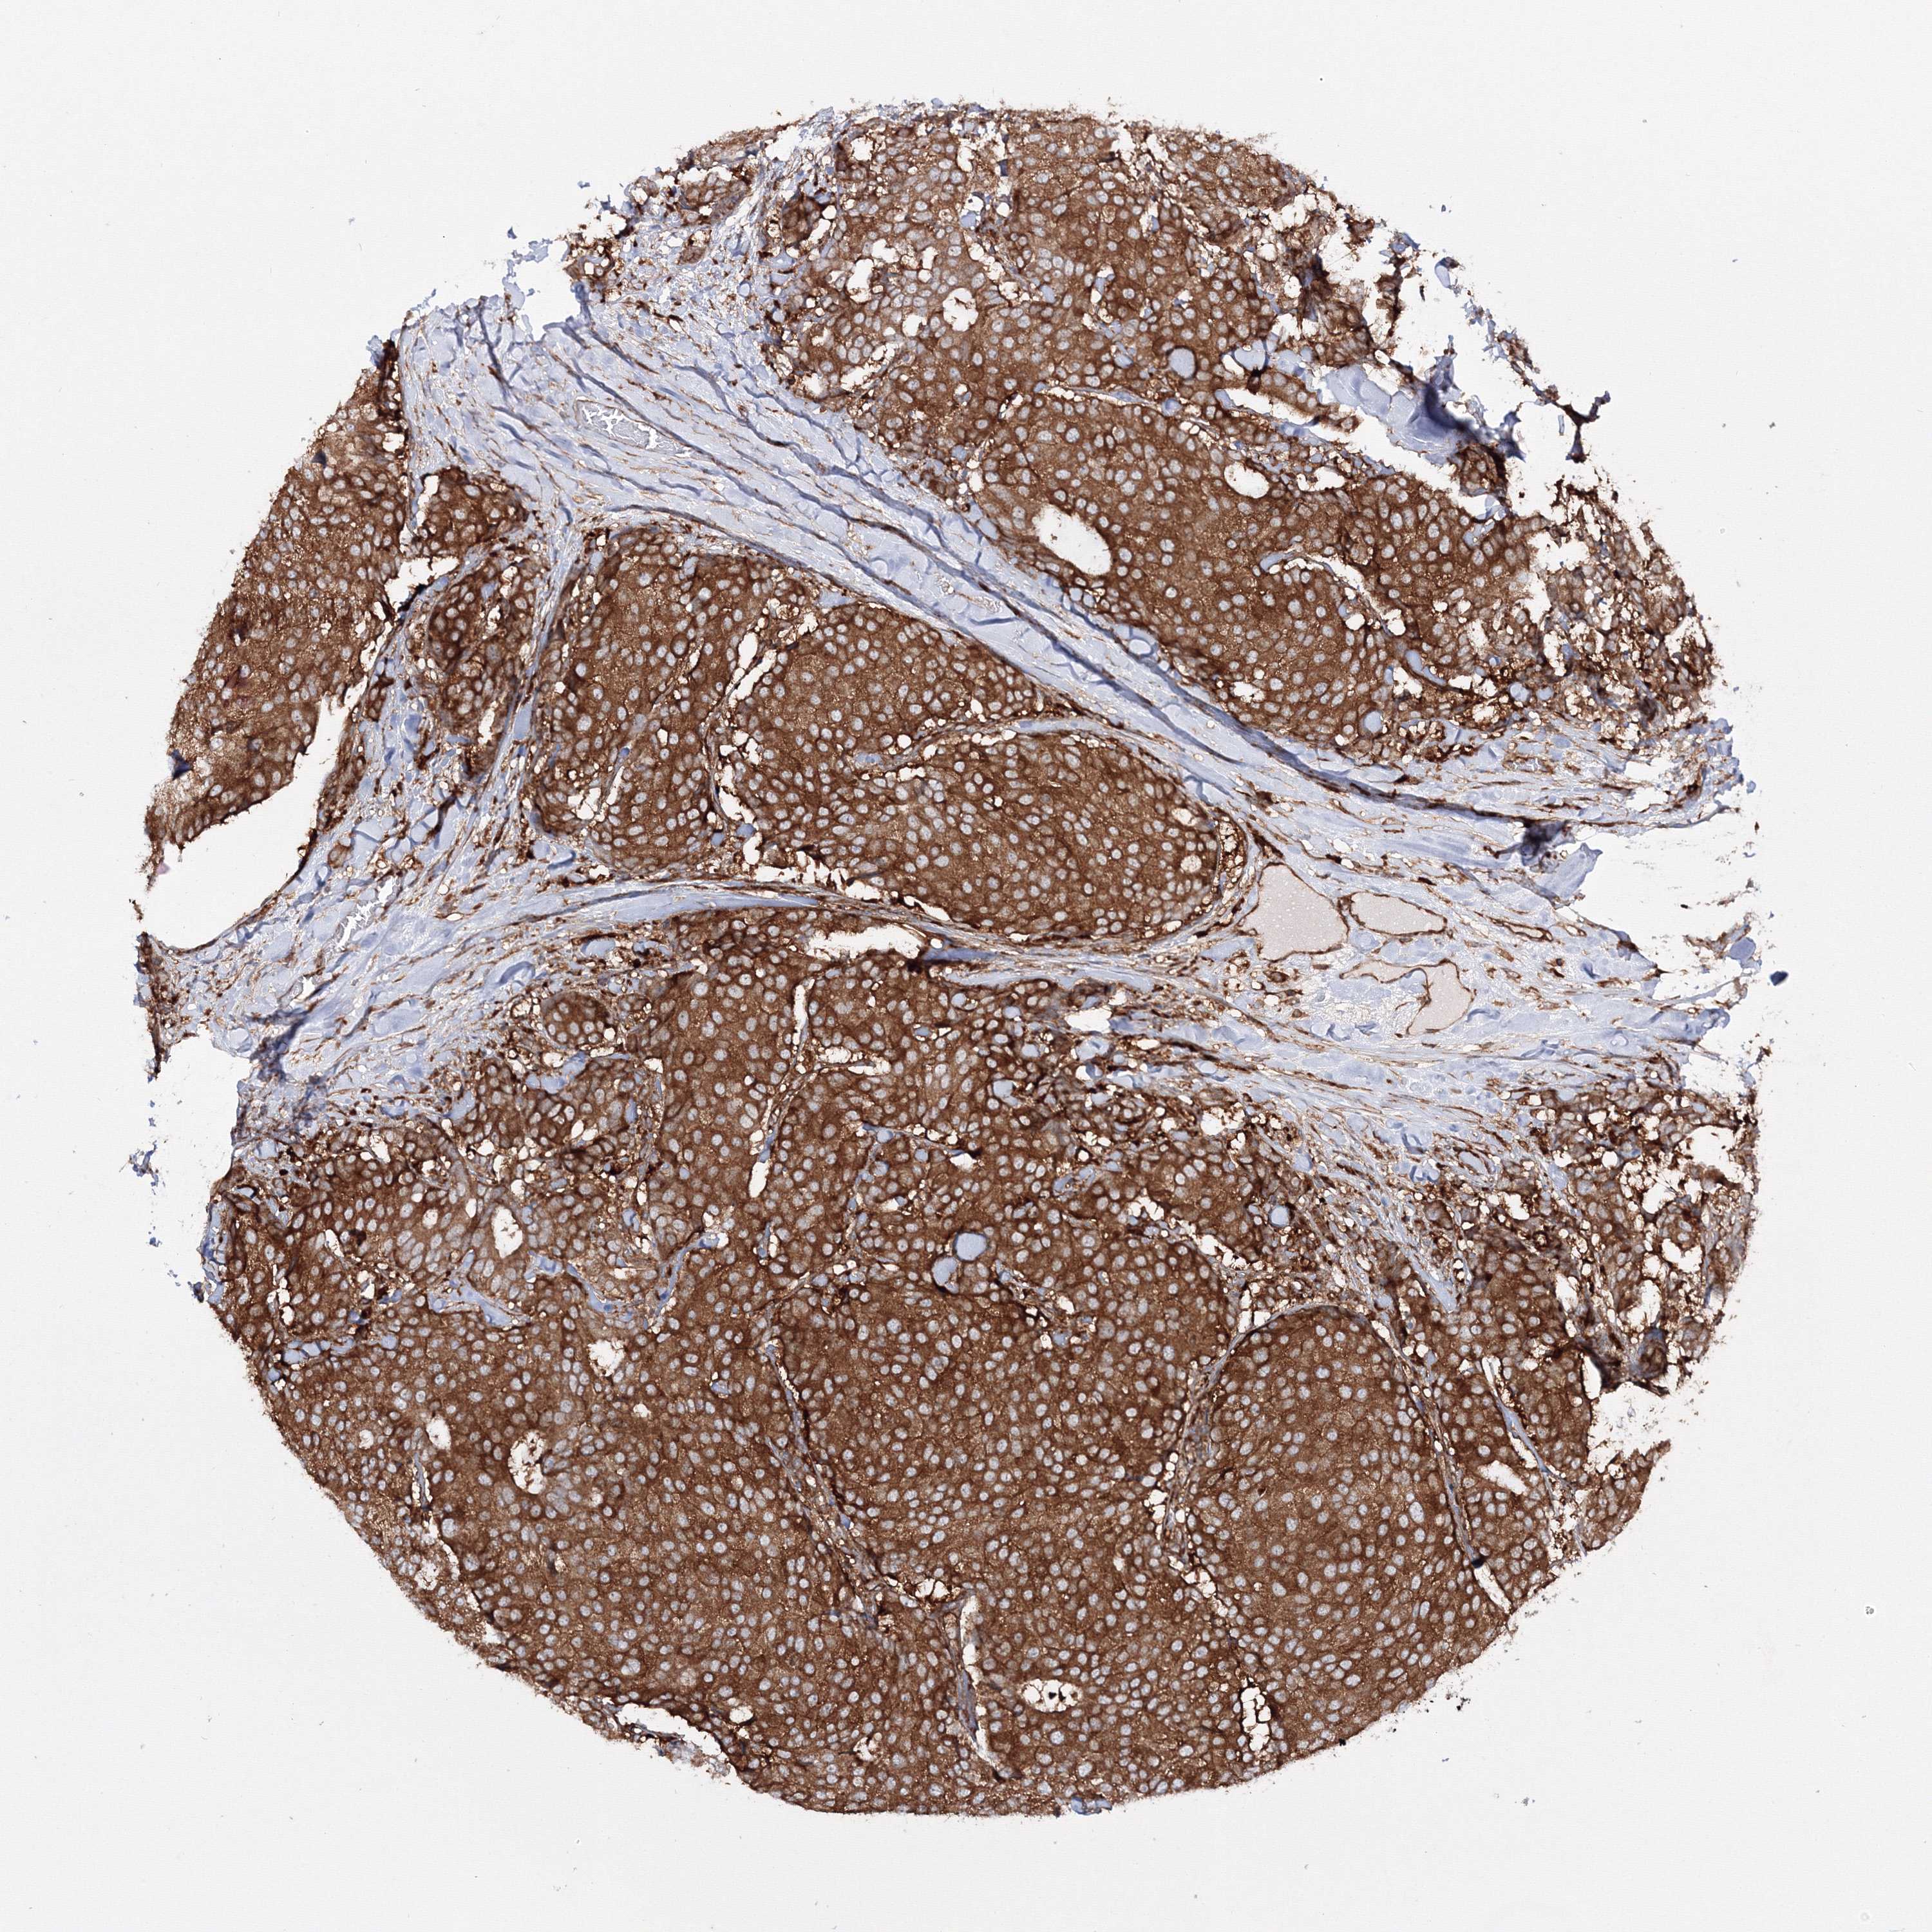

CANCER BREAST CANCER Show tissue menu

BRCA TCGA BRCA VALIDATION PROTEIN EXPRESSION